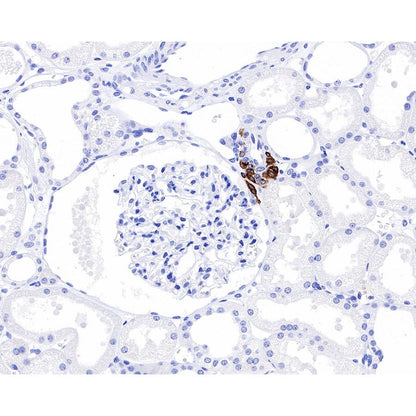

IHC shows positive staining in paraffin-embedded human kidney. Anti-Renin antibody was used at 1/1000 dilution, followed by a HRP Polymer for Mouse & Rabbit IgG (ready to use). Counterstained with hematoxylin. Heat mediated antigen retrieval with Tris/EDTA buffer pH9.0 was performed before commencing with IHC staining protocol.

Renin is a central hormone in the control of blood pressure and various other physiological functions. The main source of renin is the juxtaglomerular cells (JGCs), which release renin from storage granules [PMID: 12949225].